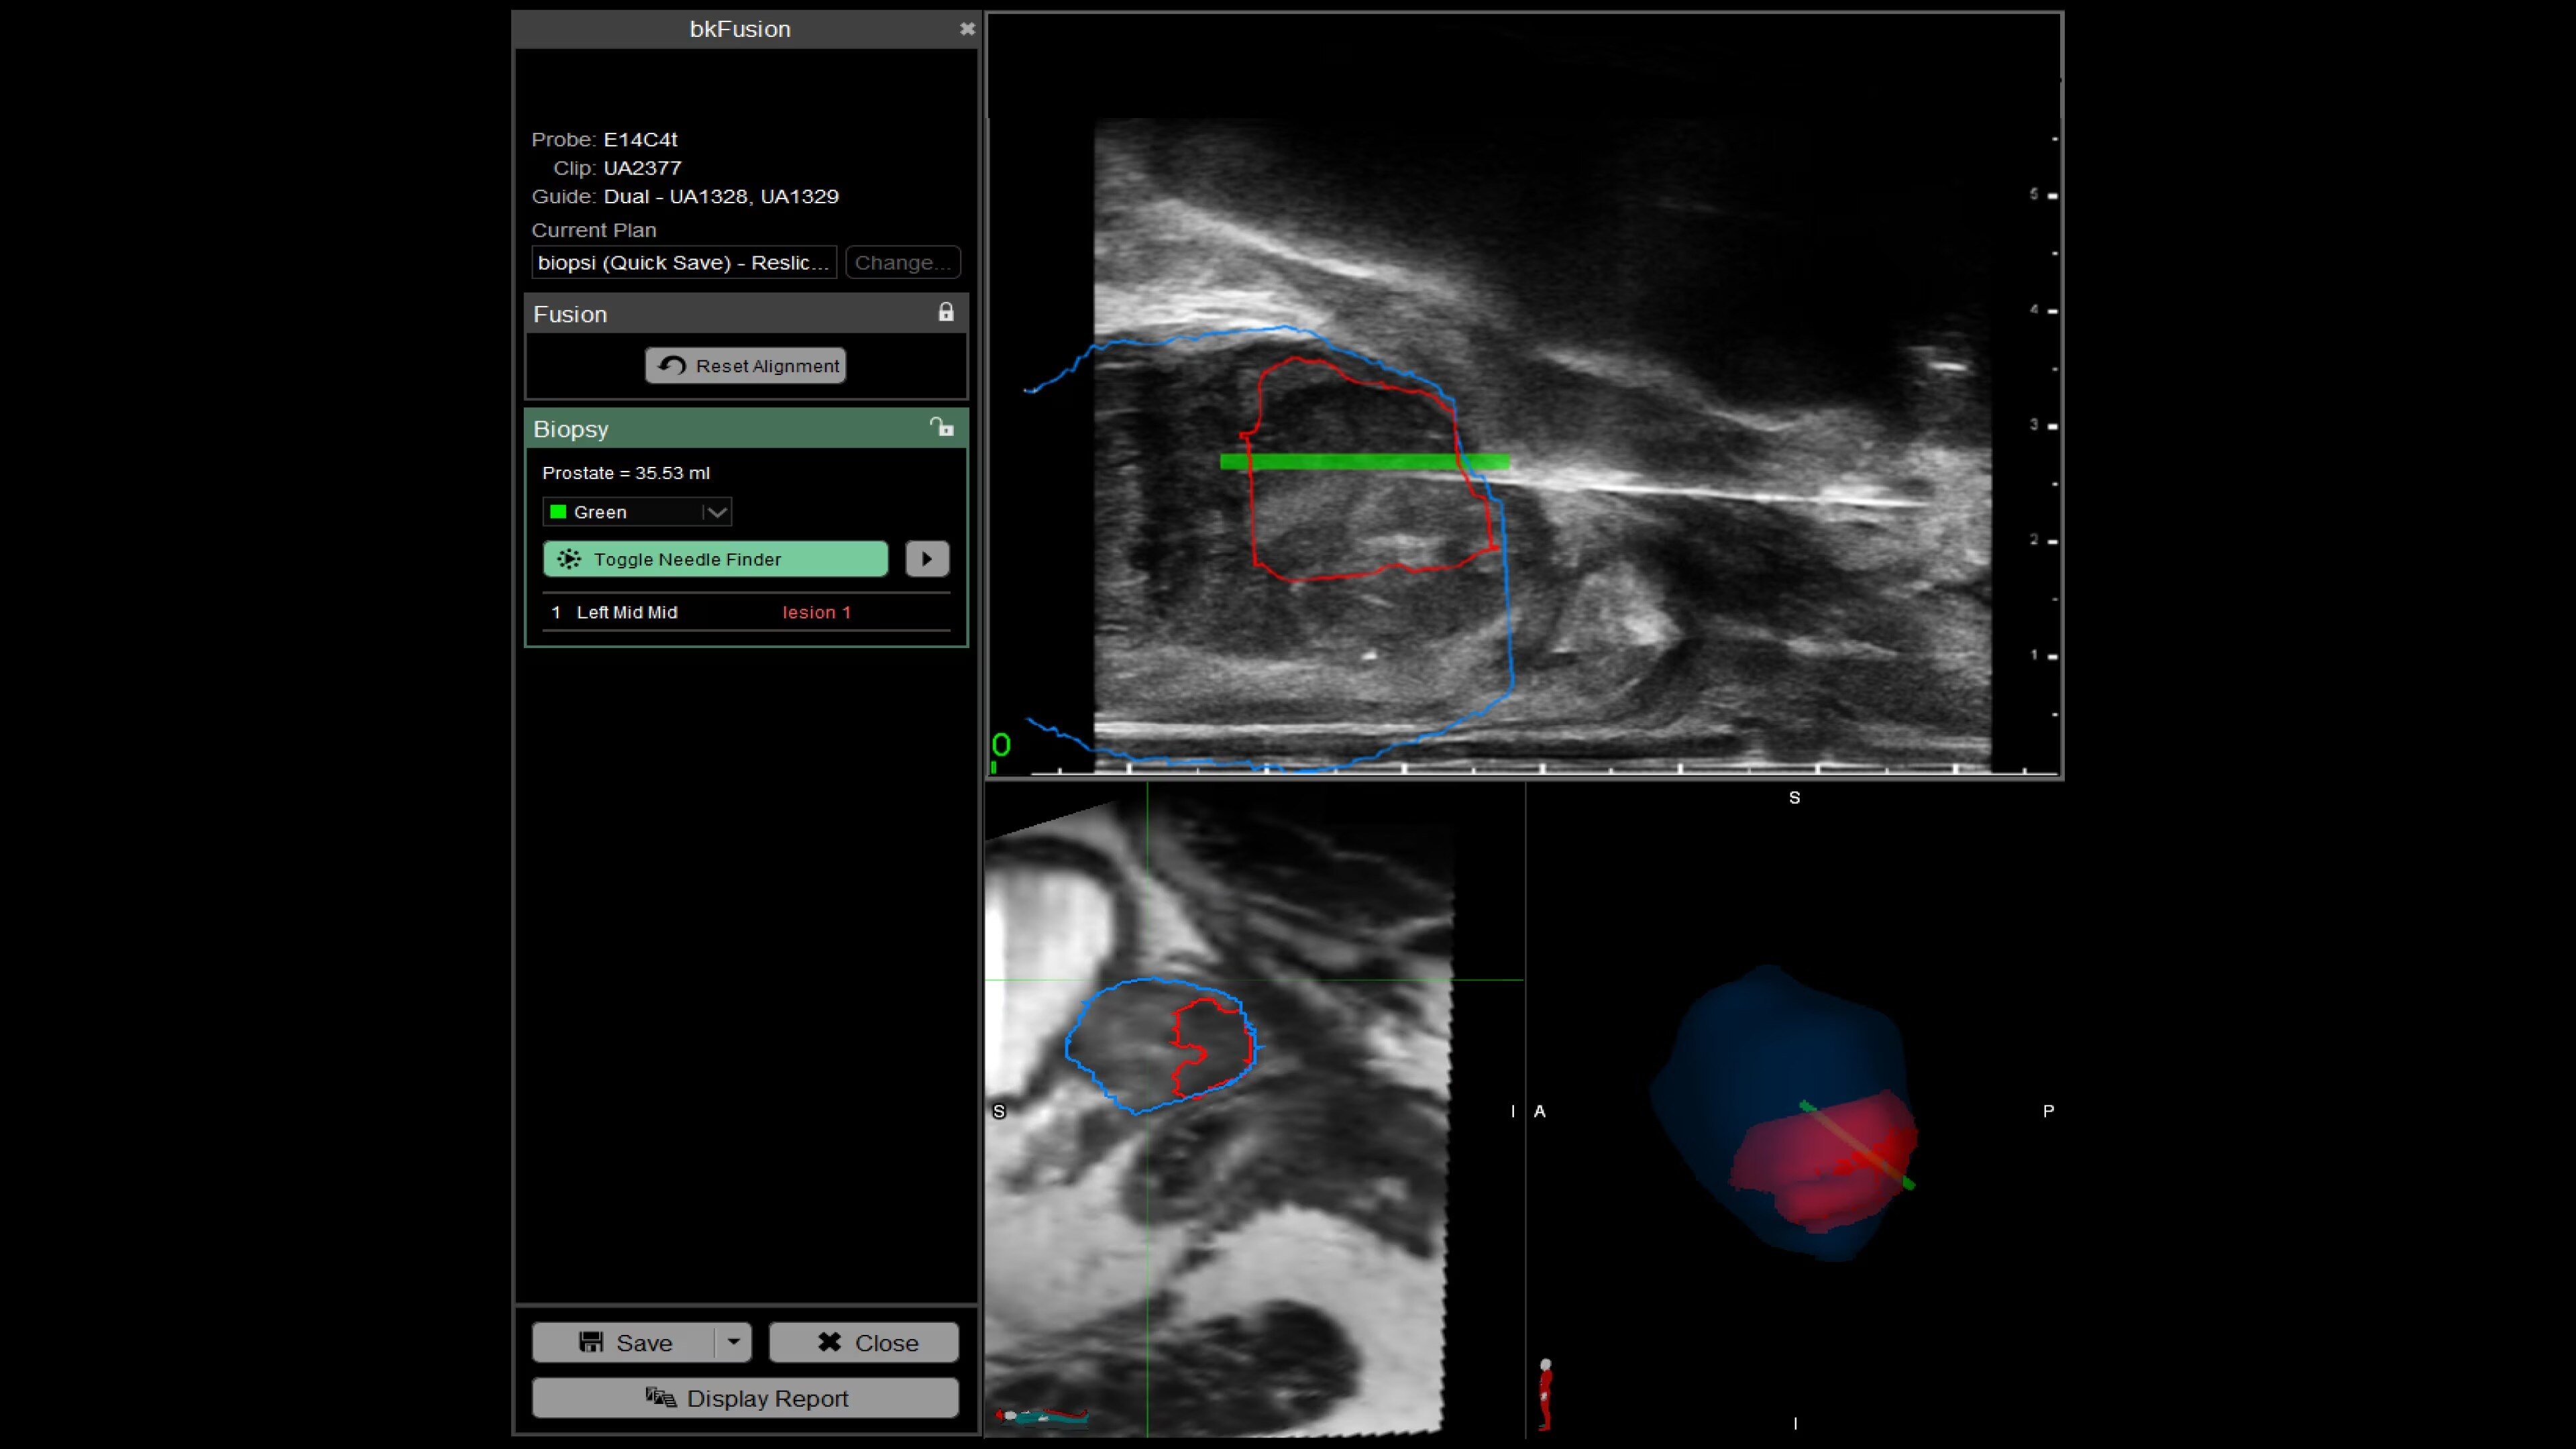

bkFusion–MRI-ultrasound Fusion Biopsy Solution

bkFusion offers advanced MRI-ultrasound fusion for high precision prostate biopsies. Benefit from high spatial resolution, fast workflow, and flexible biopsy options.

bkFusion is a fast, flexible, and effective MRI-ultrasound fusion prostate biopsy solution. Clinically proven to have effective detection rates¹, bkFusion offers a streamlined workflow designed for urologists. It provides the flexibility to choose from a range of options for transperineal and transrectal prostate biopsies. bkFusion is the only MRI-ultrasound fusion solution guaranteed to work with your ultrasound system, powered by unique Predictive Fusion® software for reliable image registration.

With bkFusion, confidently target your biopsy with clear visualization of organ borders to detect registration errors or deformations in real-time. bkFusion, MRI-ultrasound fusion biopsy solution features proprietary imaging algorithms developed with high spatial, temporal, and contrast resolution for advanced visualization.

bkFusion has proven to accurately detect 84% of PIRADS 3-5 lesions and up to 81% GG>=2 cancer.¹

Enhance biopsy accuracy with Predictive Fusion®

Predictive Fusion® is the proprietary registration method allowing you to imediately see any errors in the overly of MRI and ultrasound images before and during the procedure. Utilizing rigid 2D slice registration, it eliminates distortion in merging 3D shapes, ensuring precise MRI-ultrasound fusion. If changes are needed, make simple, one-touch, micro-adjustments to updte the registration without calibration steps or 3D sweeps. Enhance your prostate biopsy accuracy with this advanced technology.